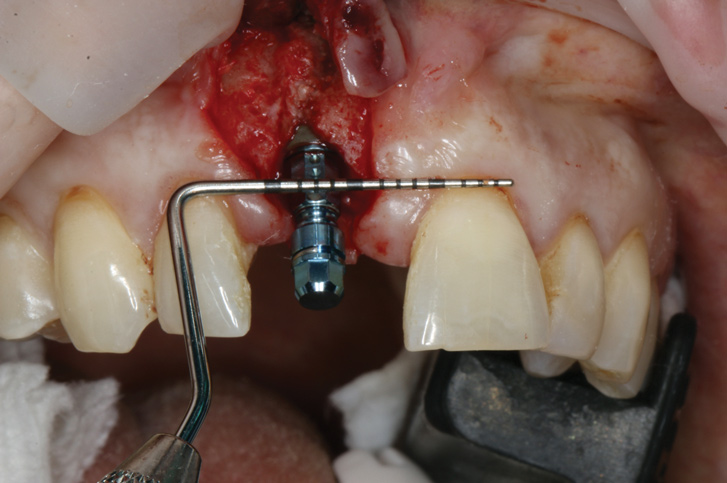

(17.) Implant placed 1-mm distal to the midline of the edentulous space, corresponding with the planned location of the gingival zenith. Note the lack of sufficient bone buccal to the implant that necessitated further grafting.

Figure 17